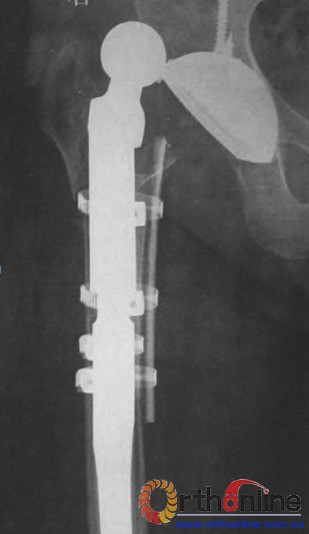

在2008年以前,多使用28 mm股骨头假体进行翻修,而2008年以后,除了个别使用加强环的患者外,多采用36 mill股骨头假体翻修。28 mm组患者均获得随访,随访时间33~71个月。平均43.3个月;共出现7髋脱位,脱位率为6.2%(7/112);其中使用加强环翻修者脱位2髋,脱位率9.5%(2/21);使用打压植骨技术翻修者脱位3髋,脱位率为8.3%(3/36);使用生物臼翻修者脱位2髋(图1),脱位率为3.6%(2/55)。36 him组患者均获得随访,随访时间12—37个月,平均26.7个月;仅1髋出现脱位,脱位率为2.2%(1/46),但此例患者臀中肌在初次置换中被损坏,患者髋关节感染后只行了清创旷置手术,在感染控

图1使用MP股骨假体结合28 Inlll股骨头和生物固定杯翻修后脱位